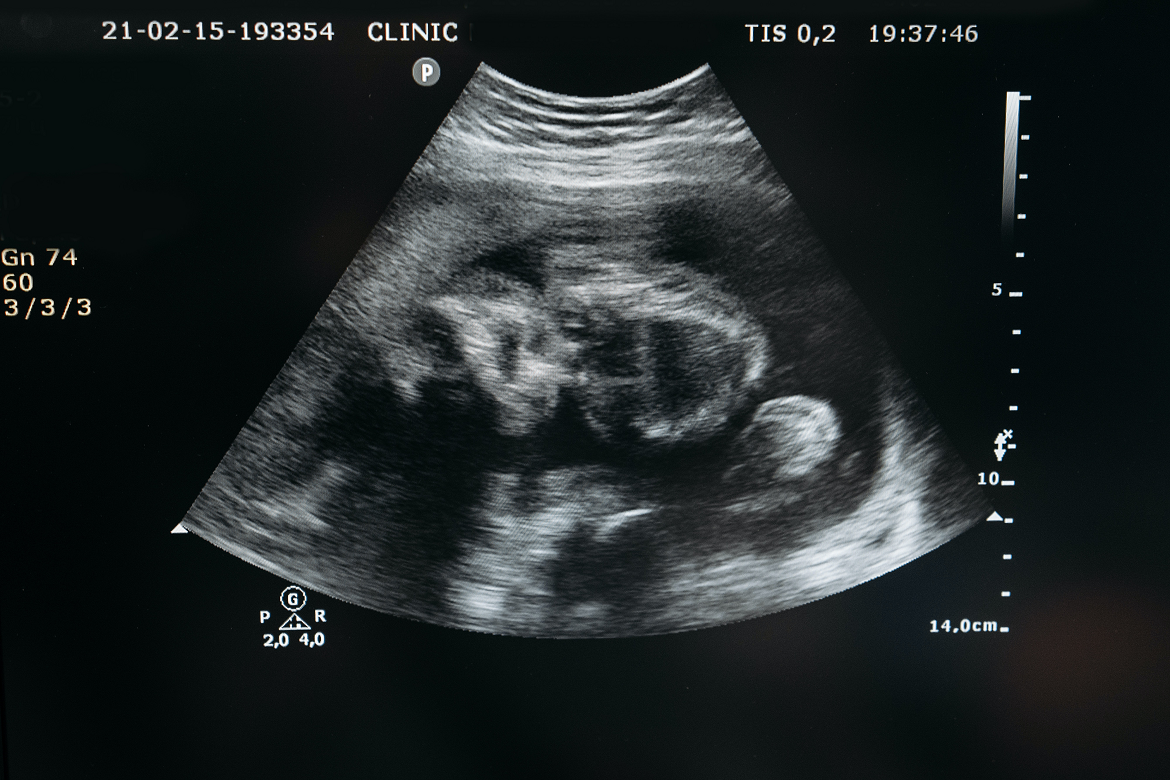

Badanie ultrasonograficzne (USG) to najpopularniejsza i najczęściej wybierana metoda poznania płci dziecka w Polsce. To fascynujące, jak za pomocą fal dźwiękowych możemy zajrzeć do wnętrza brzucha i zobaczyć naszego maluszka. Płeć może być widoczna na różnych etapach ciąży, a ja postaram się wyjaśnić, kiedy i z jaką pewnością możemy liczyć na tę informację.

Jeśli chodzi o określenie płci za pomocą USG, USG połówkowe, przeprowadzane między 18. a 22. tygodniem ciąży, jest w Polsce uważane za "złoty standard". To właśnie w tym okresie, który przypada na 5. miesiąc ciąży, narządy płciowe dziecka są już na tyle wykształcone i widoczne, że ich identyfikacja jest możliwa z bardzo wysoką pewnością, często przekraczającą 95-99%. Oczywiście, kluczowe jest tu ułożenie płodu jeśli maluch współpracuje i nie zasłania się, wynik będzie pewny.

Podczas badania USG lekarz zwraca uwagę na zewnętrzne narządy płciowe dziecka. U chłopców widoczne są prącie i moszna, natomiast u dziewczynek charakterystyczne są wargi sromowe. Specjalista, dzięki swojemu doświadczeniu i precyzji sprzętu, jest w stanie odróżnić te struktury i z dużą pewnością określić płeć.